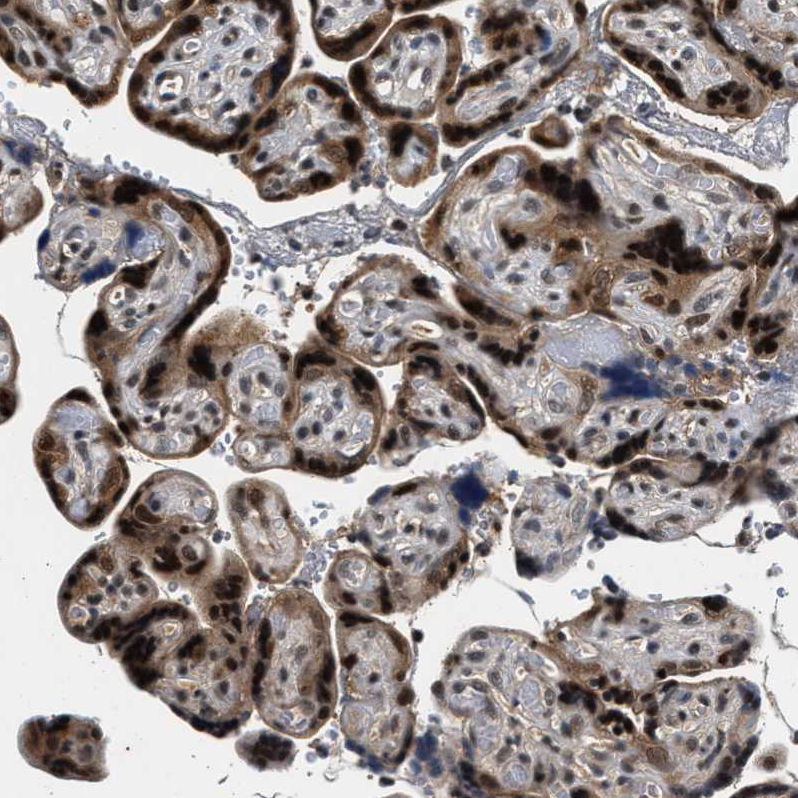

Immunohistochemical staining of human cerebellum shows moderate nuclear positivity in Purkinje cells.